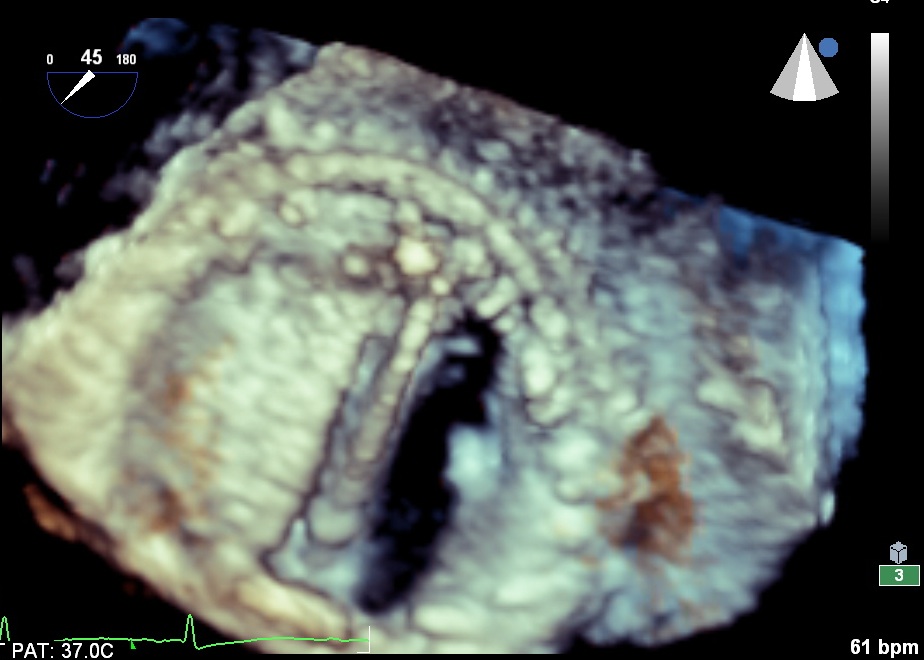

Ailette bloquée!

Bon, je vous rassure, ce n’est pas la même patiente, (cette dernière photo concerne une thrombose aiguë obstructive de prothèse en post-opératoire précoce pour une endocardite mitrale, avec un syndrome inflammatoire majeur). Une des deux ailettes est totalement bloquée en position fermée.

Pour les mouvements des ailettes d’une prothèse mitrale, même avec de l’habitude, il n’est pas toujours évident de certifier qu’une ailette est bloquée, de peur de ne pas être exactement dans le plan ou l’ouverture est bien symétrique, particulièrement si l’oreillette est petite, ou si le plan d’implantation de la prothèse est inhabituel. Le 3d, s’affranchissant totalement du « plan », puisqu’on acquière un volume, permet de lever ces doutes et la prise en charge qui découle de l’examen est plus claire.